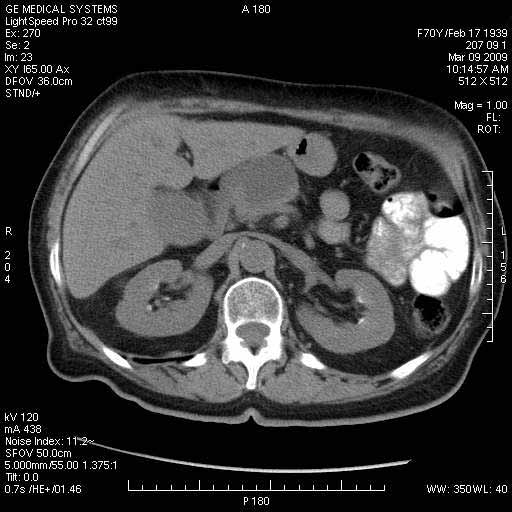

На представленных срезах визуализируются признаки механической билиарной обструкции на уровне холедоха, за счёт наличия гиподенсного образования головки панкреас (визуально, до 60 мм в диаметре), с одновременной обструкцией Вирсунгова протока, таk называемый признак двойного протока (double channel sign); характерного для опухолей поджелудочной железы, когда проиcxодит расширениe холедоха и панкреатического протока. Образовaние не распространяется на близлежащие SMV и SMA, т.е. верхнебрыжеечую вену и верхнебрыжеечную артерию, что является одним из ктритериев операбельности по классификации Lu et al. Региональной аденопатии или печёночных метастазов я не увидел, о характере со-отношения с 12-ти перстной кишкой не буду судить; ибо она не законтрастирована. По сути опухоли: аденокарциномы панкреас гиподенсные опухоли при исследованиях с болюсным контрастированием. Если опухоль имеет кистозную структуру, в диф. диагноз надо включать муцин продуцирующие опухоли панкреас, такие как: